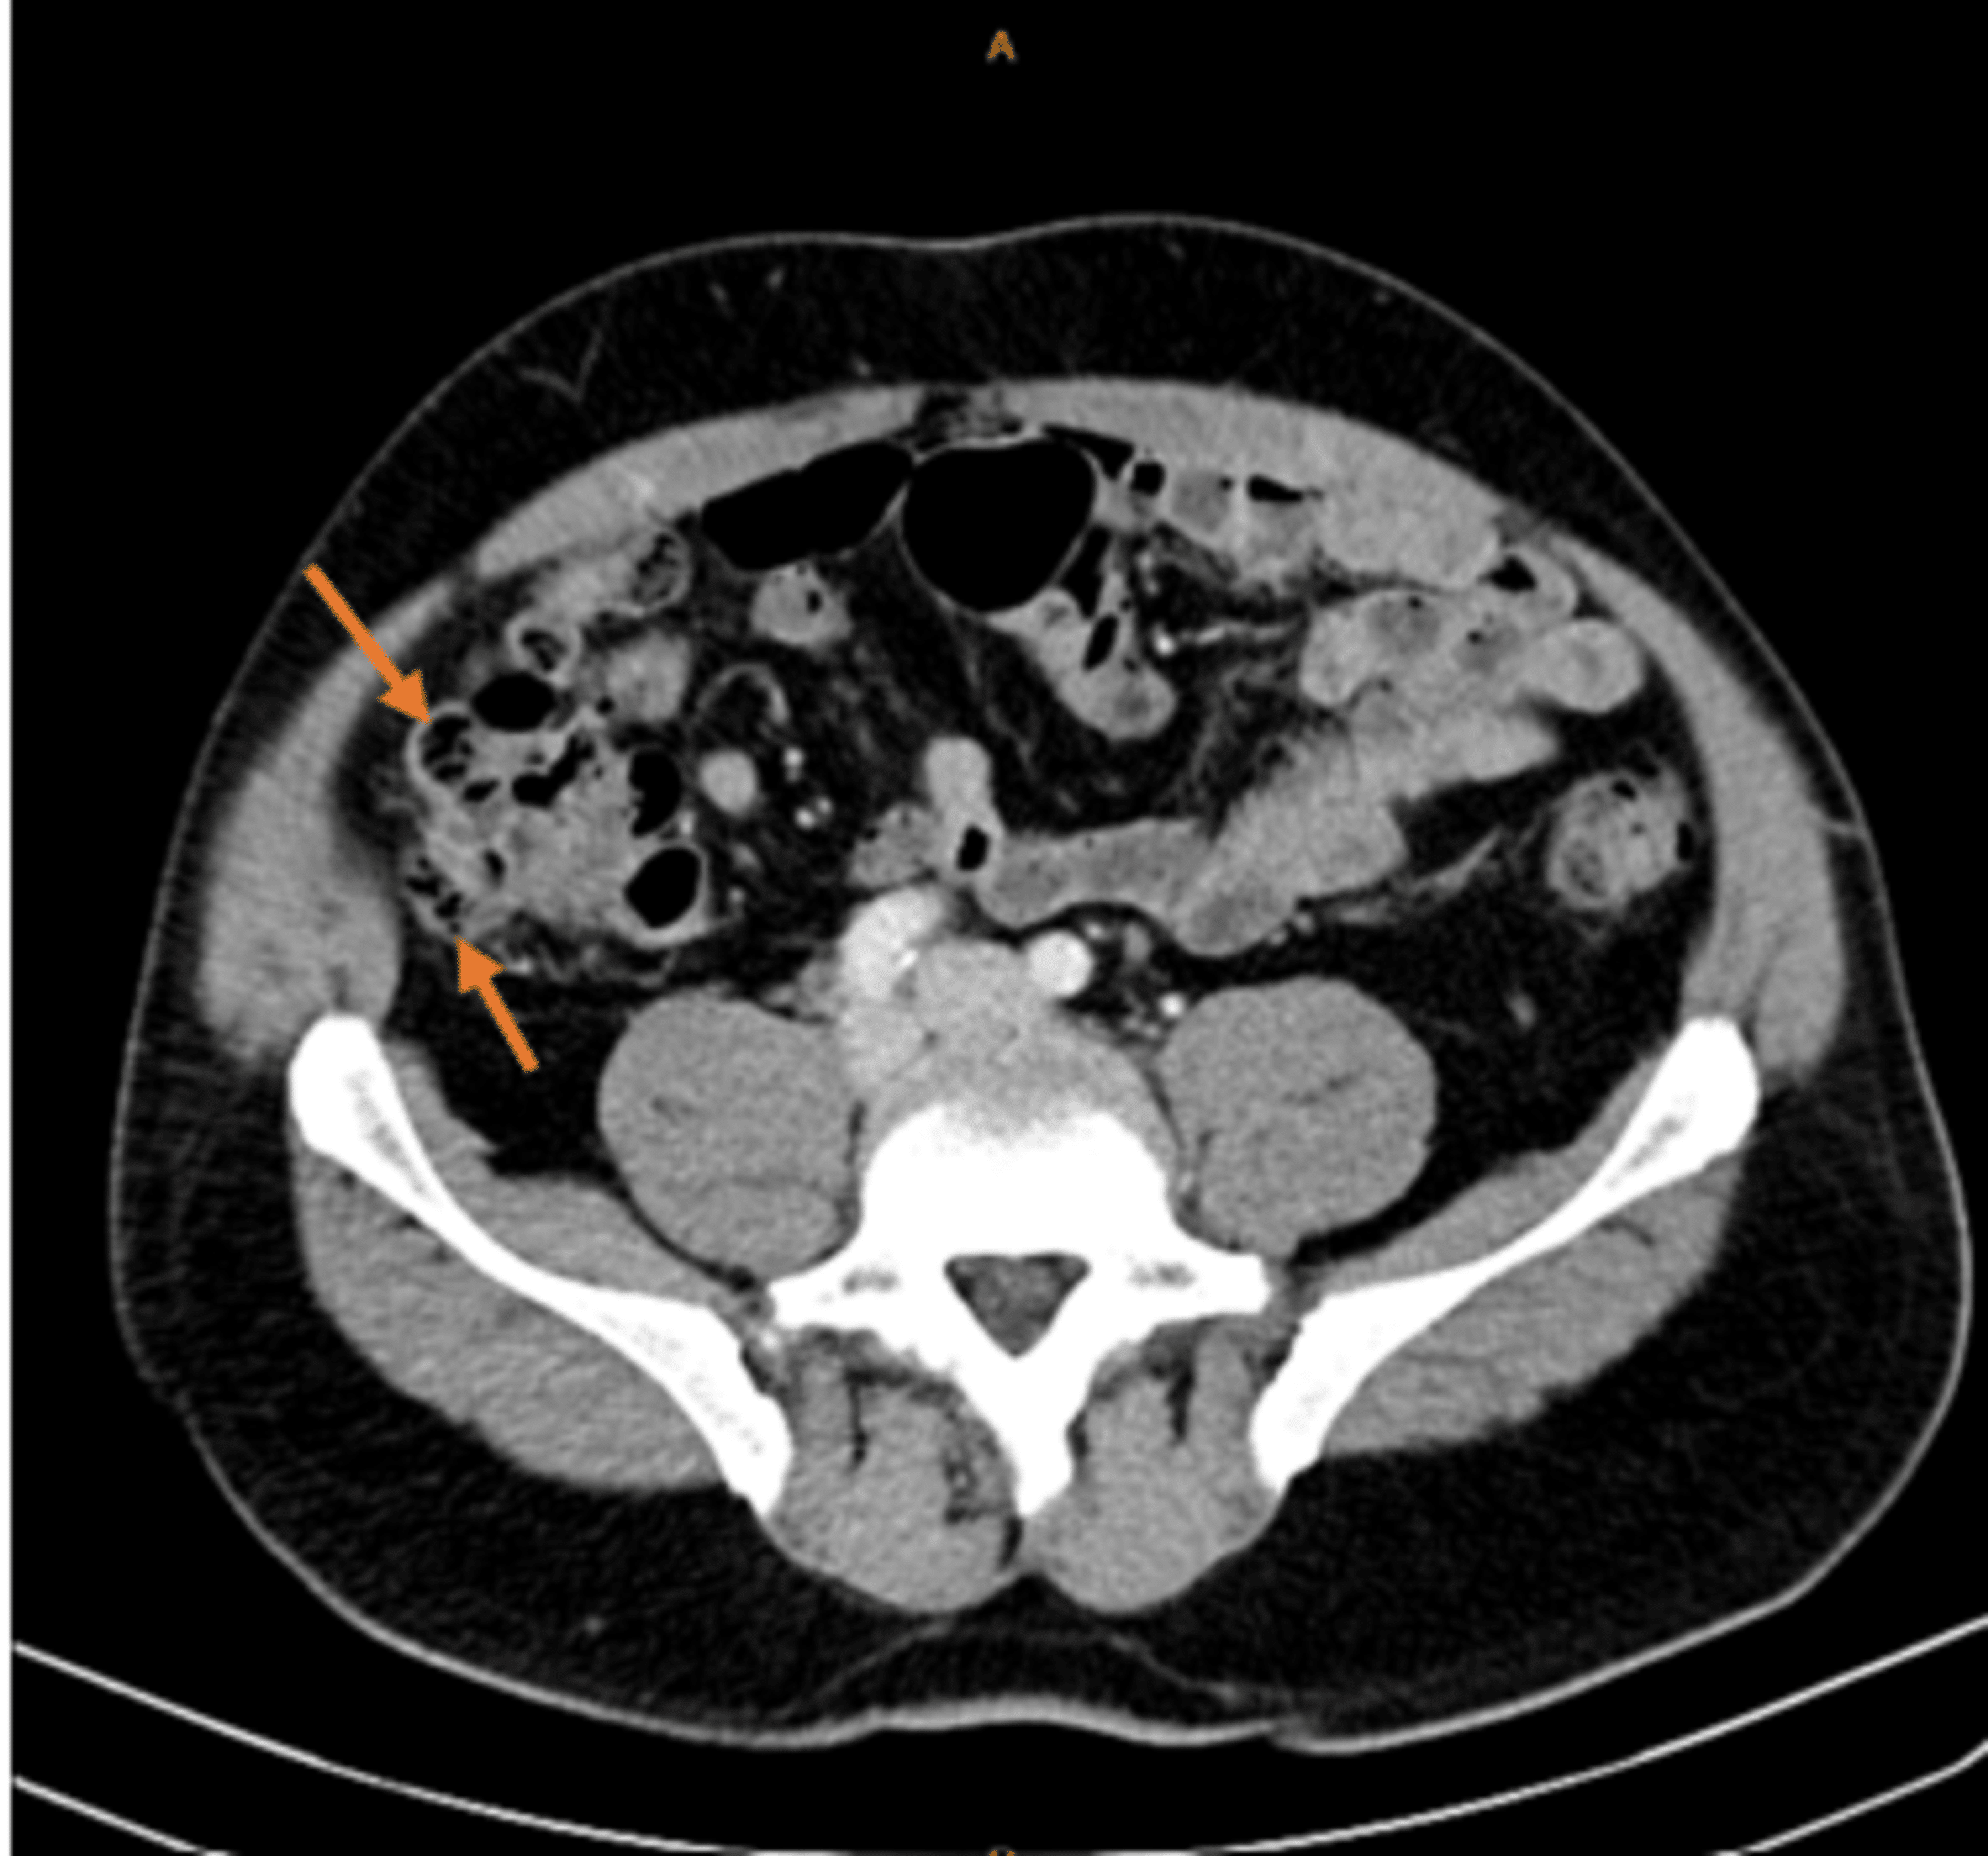

From radiologykey.com

Diverticulitis Radiology Key Lettuce Causing Diverticulitis no specific foods are known to trigger bouts of diverticulitis symptoms, also called attacks. Your doctor can tell you whether you can eat salad when you're having a diverticulitis. Diverticulitis (also referred to as a. diverticulosis happens when small pouches (diverticula) form in the walls of the colon. And no special diet has. diverticulitis is a condition. Lettuce Causing Diverticulitis.

From www.cureus.com

Cureus RightSided Diverticulitis A Rare Cause of RightSided Lettuce Causing Diverticulitis Diverticulitis (also referred to as a. diverticulosis happens when small pouches (diverticula) form in the walls of the colon. no specific foods are known to trigger bouts of diverticulitis symptoms, also called attacks. is salad bad for diverticulitis? While it's crucial to press pause on some veggies during a flare (and resume once symptoms diverticulitis is. Lettuce Causing Diverticulitis.

Cureus Cecal Diverticulitis in a Geriatric Patient Lettuce Causing Diverticulitis Diverticulitis (also referred to as a. diverticulitis is a condition in which the diverticula, small, bulging pouches or sacs that grow inside the walls of your colon (large intestine), get. no specific foods are known to trigger bouts of diverticulitis symptoms, also called attacks. While it's crucial to press pause on some veggies during a flare (and resume. Lettuce Causing Diverticulitis.

Cureus Colonic Diverticulitis Complicated by Stenosis Causing Bowel Lettuce Causing Diverticulitis diverticulitis is a condition in which the diverticula, small, bulging pouches or sacs that grow inside the walls of your colon (large intestine), get. Diverticulitis (also referred to as a. is salad bad for diverticulitis? diverticulosis happens when small pouches (diverticula) form in the walls of the colon. And no special diet has. no specific foods. Lettuce Causing Diverticulitis.